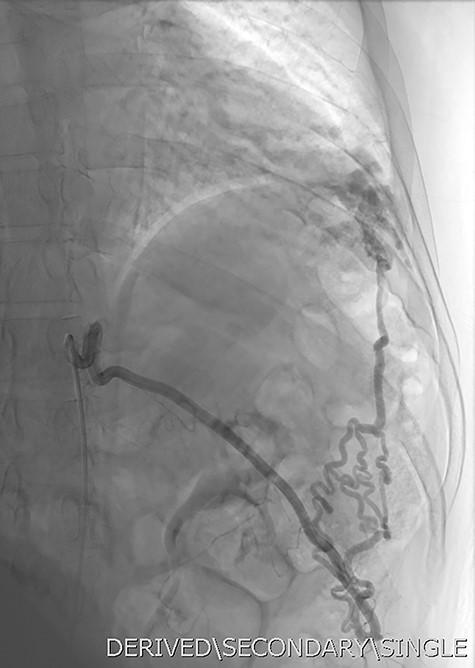

Given the findings, he was referred to Interventional Radiology for a formal digital subtraction angiogram with view of transcatheter embolization. Under local anaesthetic and sedation, a 5-french sheath was placed in the left common femoral artery. Using a 5-french pigtail catheter, aortic angiography was undertaken, confirming the CTPA findings and demonstrating predominant supply of the vascular malformation via the left intercostal arteries and the left inferior phrenic artery (Fig. 4)—draining into the left inferior pulmonary artery and vein. Superselective catheterization of the left intercostal arteries (Fig. 5) and the left inferior phrenic artery (Fig. 6) are shown. Unfortunately, due to the malformation’s volume and complexity, embolization was abandoned. He was subsequently referred to Cardiothoracic Surgery, currently awaiting consideration and workup for ligation and resection via video-assisted thoracoscopy, and potentially thoracotomy.

Aortic DSA using a pigtail catheter (green arrow), demonstrating extensive arterial collateralization between the left chest-wall intercostal arteries and the left lower lobe PAVM.